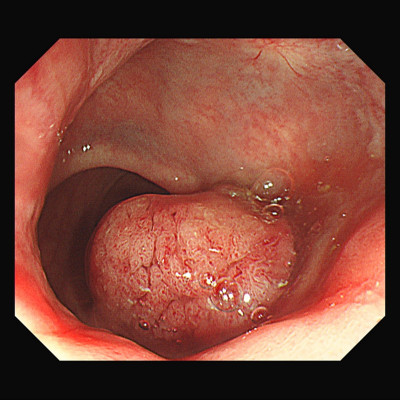

高齡82歲的黃爺爺前陣子開始只要上廁所,肛門就會出血,用手觸摸還摸得到一小塊肉,但他以為是痔瘡,不以為意,出血情況持續快1個月,在家人勸說下就醫檢查,發現黃爺爺的直腸內有一顆4.6公分大的瘜肉,無法以大腸鏡切除,醫師改以經肛門微創手術切除瘜肉,事後病理報告證實罹患大腸原位癌,不需要化療或放射線治療,

高齡82歲黃爺爺前陣子開始,只要上廁所肛門就會出血,用手摸還摸得到一小肉塊,但他總以為是痔瘡,將小肉塊推回去就好。然而出血情況持續將近1個月,家人的堅持下他才就醫,醫師檢查發現,黃爺爺的直腸內有一顆4.6公分大的瘜肉,無法透過大腸鏡切除,醫師以經肛門微創手術替他切除瘜肉,隔天就出院,最後病理報告為大